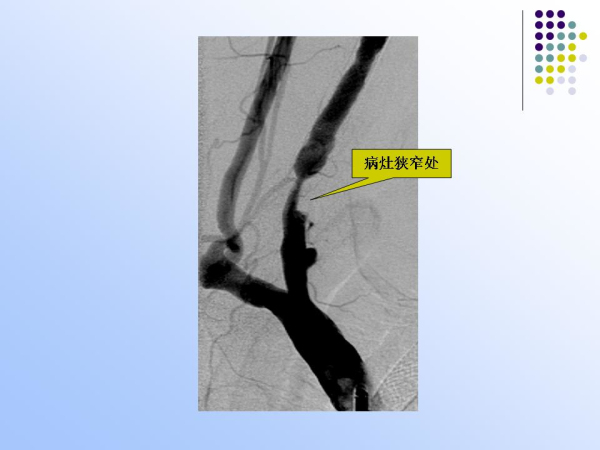

【治疗脑血管病的新技术:血管内介入治疗】—神经内科脑卒中筛查与防治办公室

脑卒中筛查与防治办公室